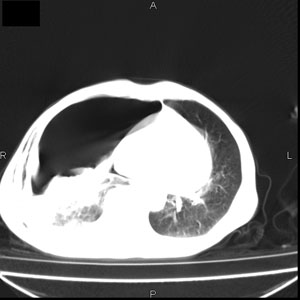

患者男,77岁,于3日前从树上摔下,头部查ct示蛛血,硬膜下出血,上腹部ct未见明显异常,右侧胸腔积液,左侧如常。肺部拍片示右侧肋骨多发骨折住院后今日来查肺部ct,我看到的是1。右侧胸腔血气胸并右肺上叶,中叶压缩性肺不张,2。右肺下叶肺挫伤并多发肋骨骨折,肌内及皮下积气3。左侧少量胸腔积液,我想请教的是3天前左侧胸腔里没有积液今天怎么出现了呢,是什么原因呢?请讨论。

张力性气胸